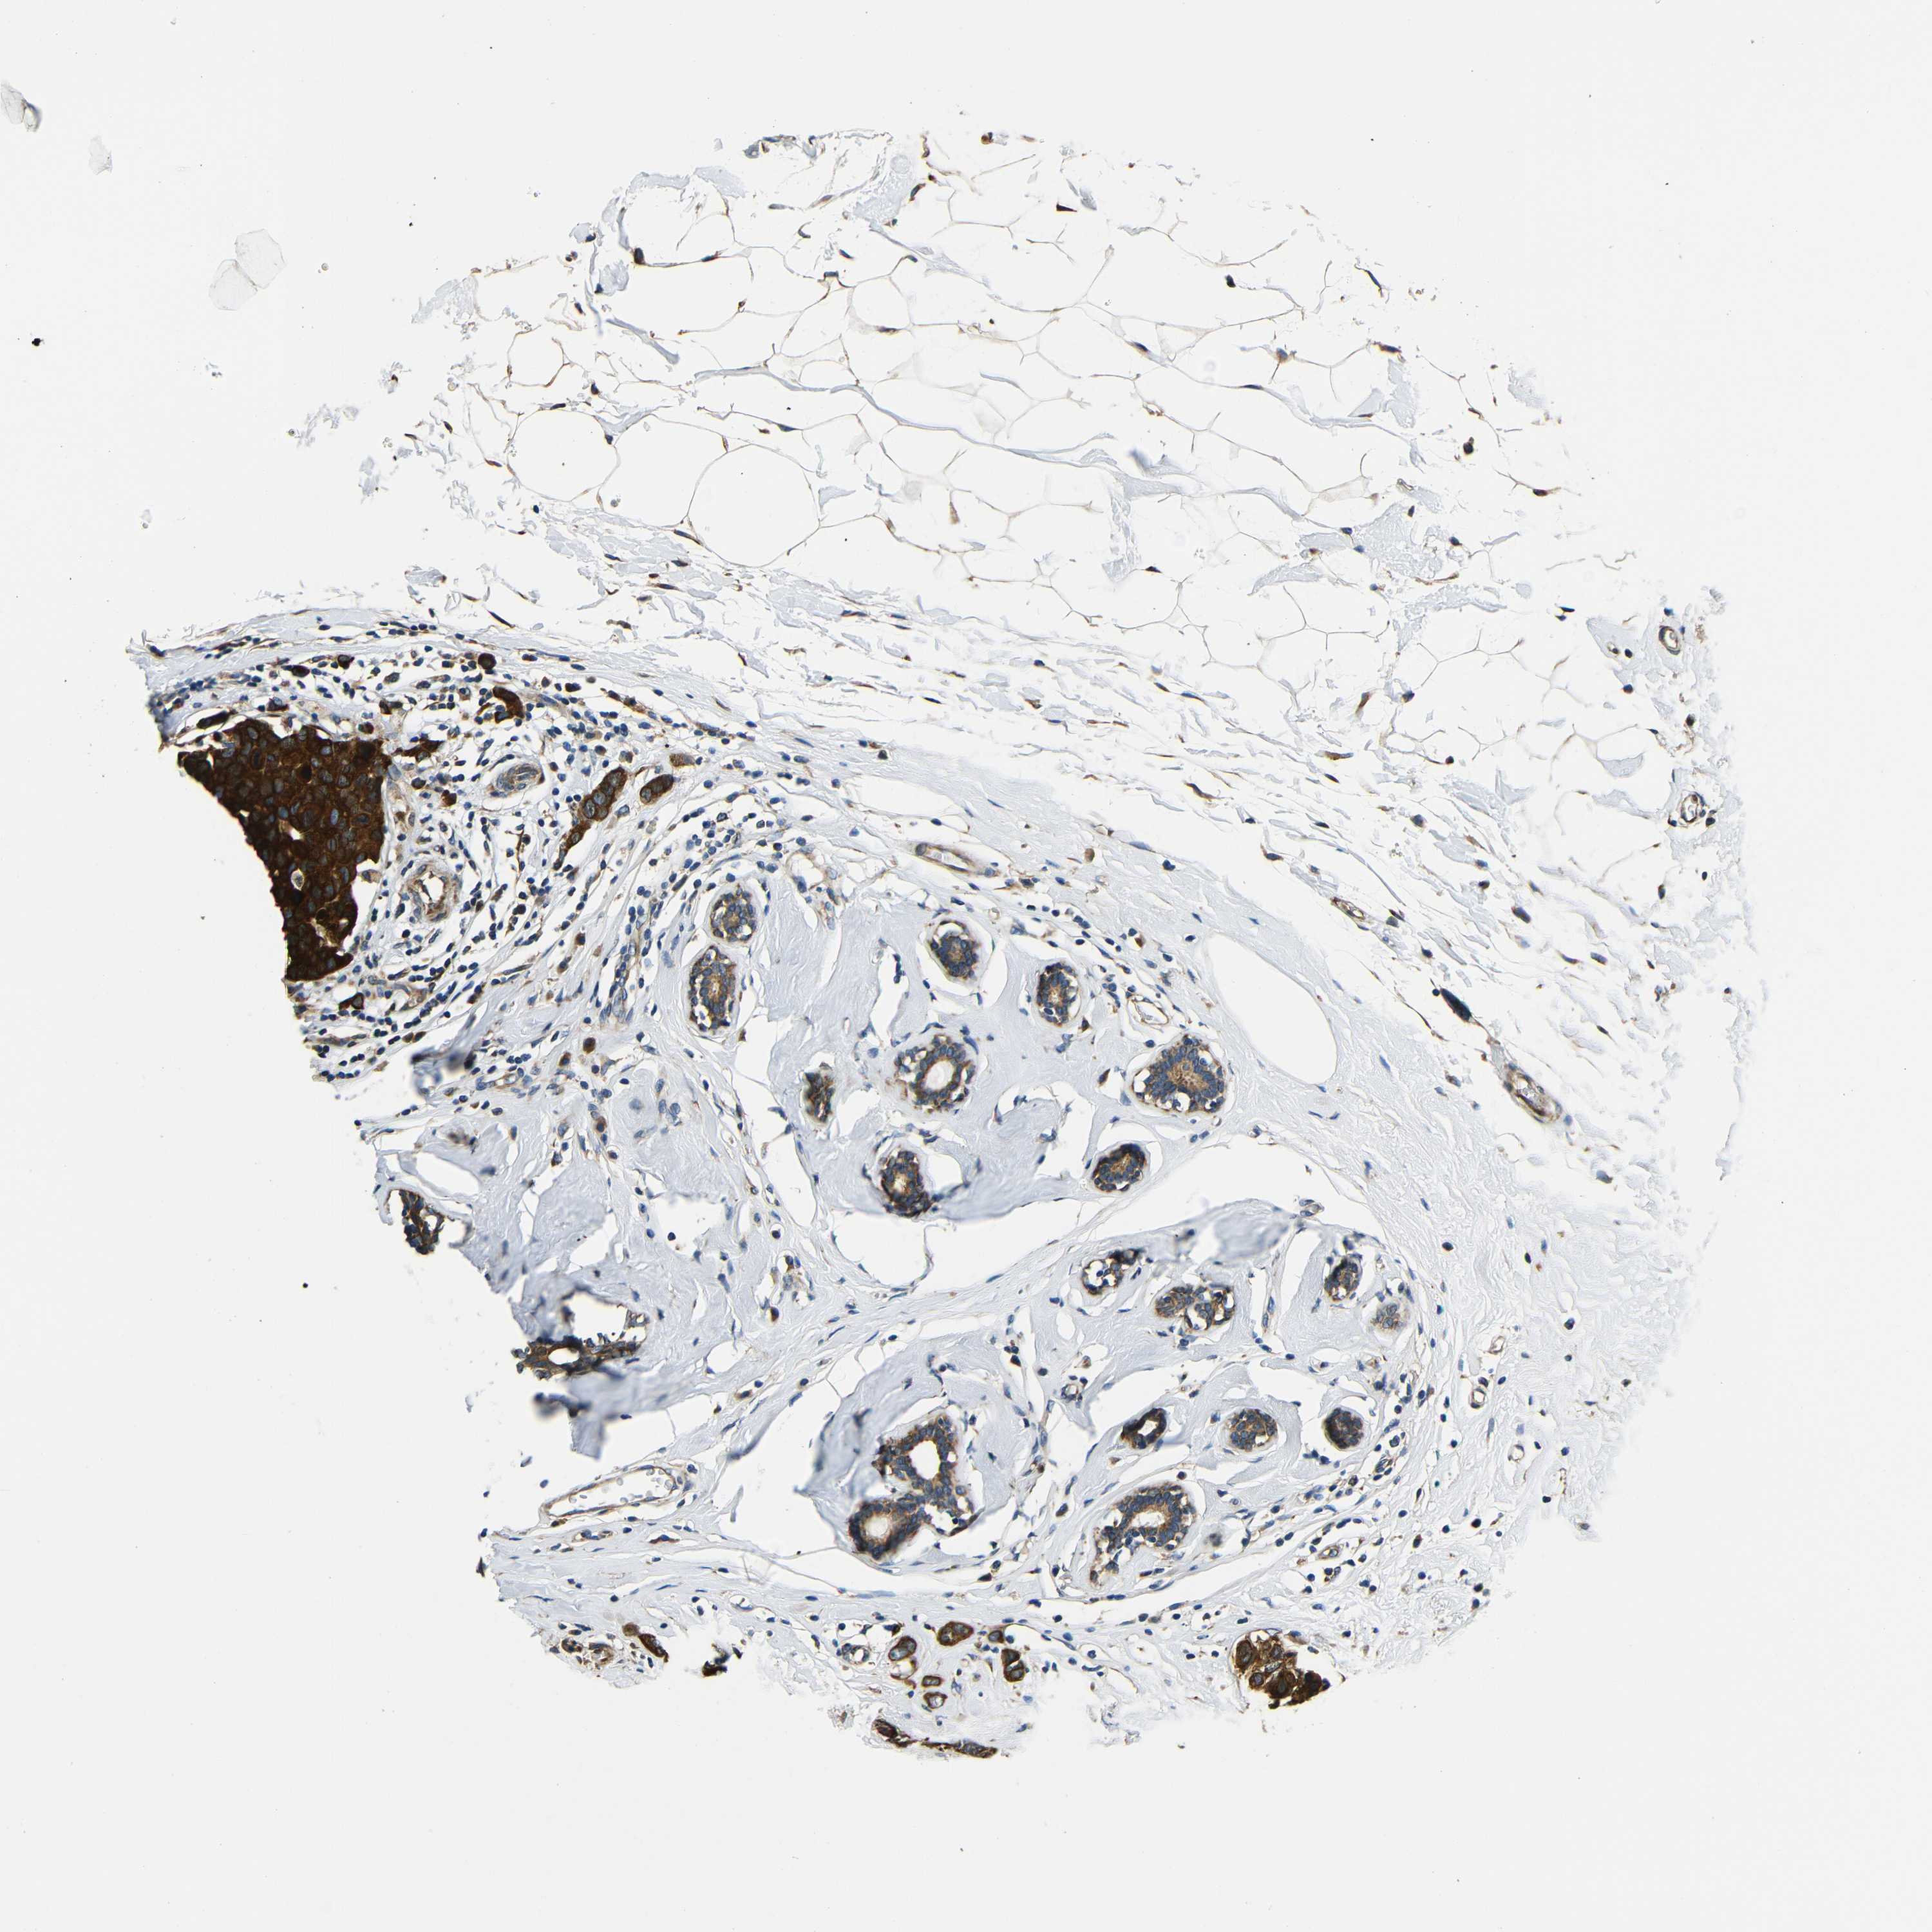

CANCER BREAST CANCER Show tissue menu

BRCA TCGA BRCA VALIDATION PROTEIN EXPRESSION